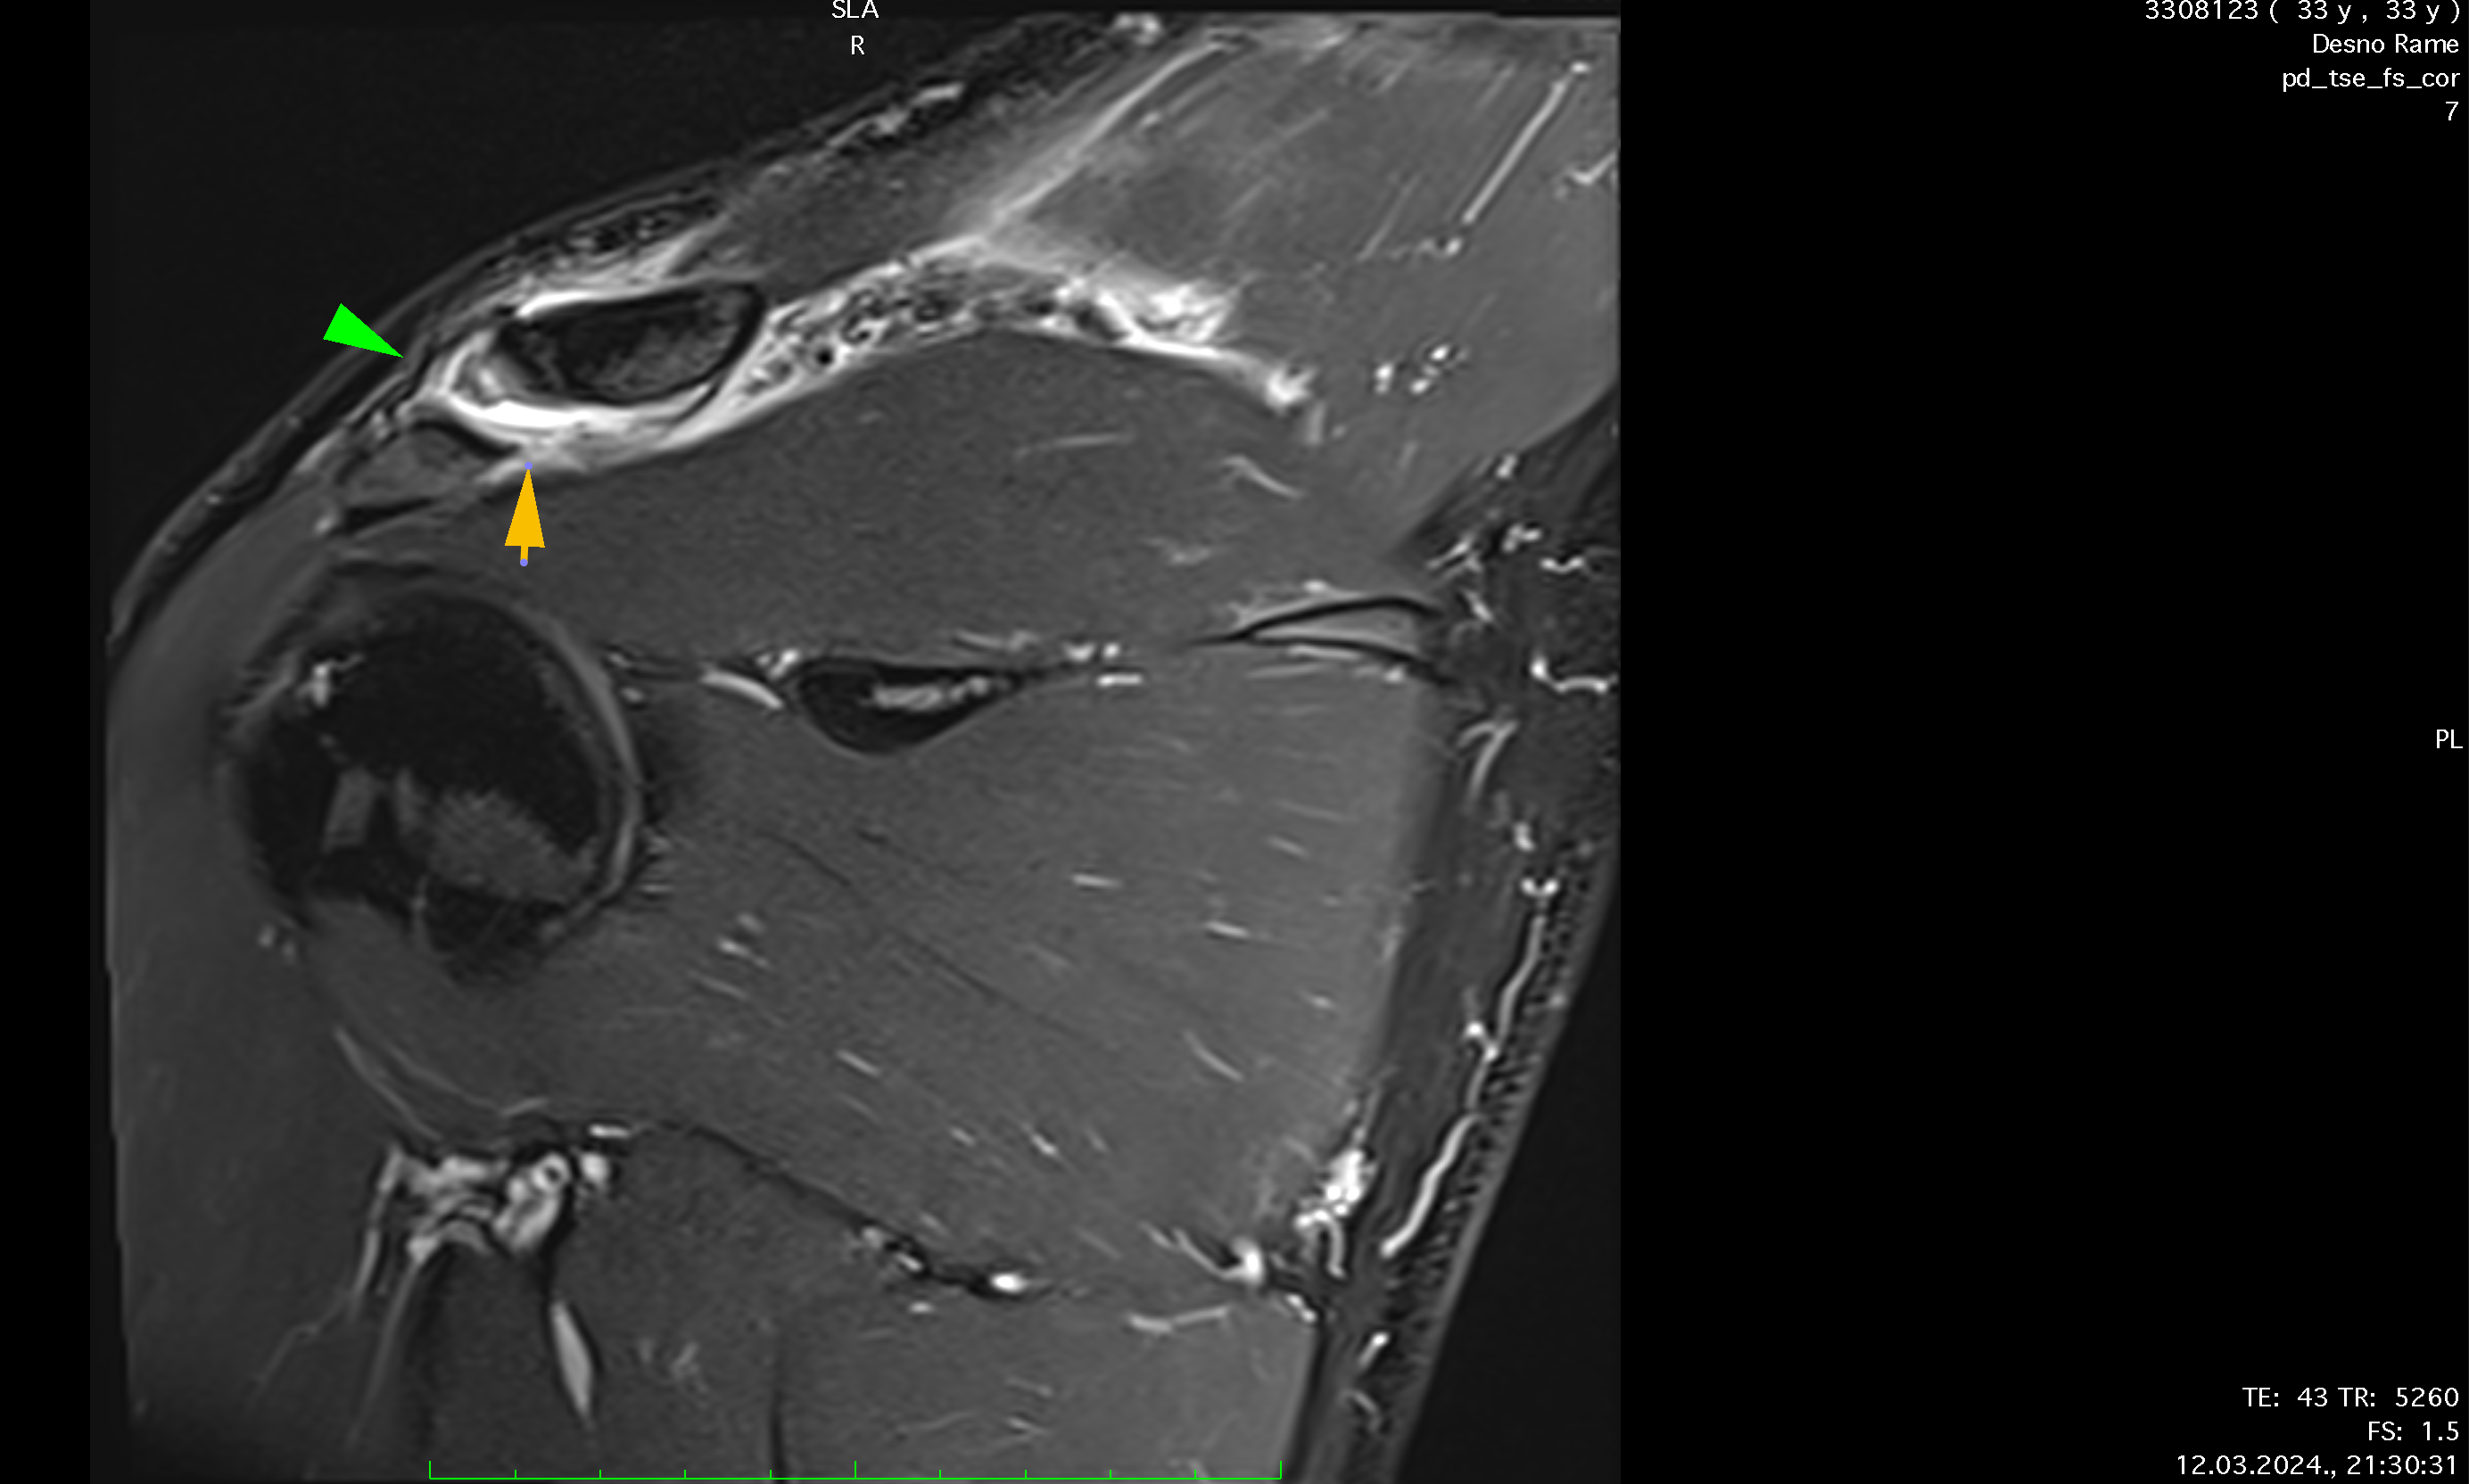

Ten days after the injury, the player's pain level had decreased to 3 out of 10, and nearly full ROM had been regained. A follow-up MRI showed significant recovery, with the AC joint fully reconnected and healed ligaments, though there was some residual edema caused by inflammation from the prolotherapy. Treatment continued for another week, during which the player engaged in more active exercises, including mobility, weight-bearing, and rotator cuff strengthening. While fast movements initially caused stiffness, this resolved within 3 to 4 days.

Reconnection of coracoclavicular ligament, soft tissue, trapezius m., regeneration, formation of AC joint capsule visible after only 8 days of therapy.